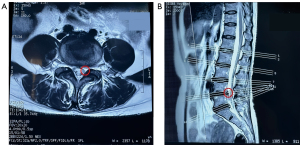

A 48-year-old female complained of radiating pain in the left buttock and left lower limb for 6 months. She was diagnosed with a lumbar disc herniation in another hospital and was recommended to undergo surgical treatment. The findings from physical examination were as follows: positive sign on Kernig’s test, which induced pain at 53°; grade IV left lower-limb myodynamia accompanied by pain and numbness in the buttock radiating to the lateral aspect of the left thigh and calf, and even the left foot; and a VAS score of 8. MRI indicated left side nerve root edema in the L4–L5 segment but no obvious disc herniation (Figure 3).